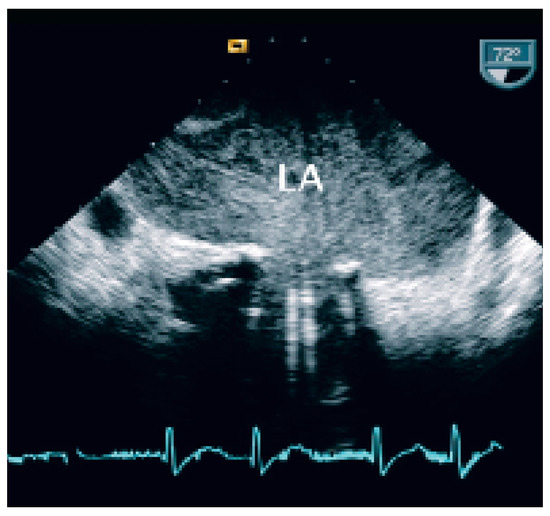

Coronary and Peripheral Thromboembolism from a Giant Left Atrium

by Marcello Di Valentino, Andrea Menafoglio, Ludwig von Segesser, Jeanne-Marie Segatto and Augusto Gallino

Cardiovasc. Med. 2006, 9(1), 28; https://doi.org/10.4414/cvm.2006.01144 - 27 Jan 2006

Abstract

We report the case of a patient with a history of mitral valve replacement and a giant left atrium with acute transmural anterior myocardial infarction and concomitant acute occlusion of the right superficial femoral artery [...] Full article